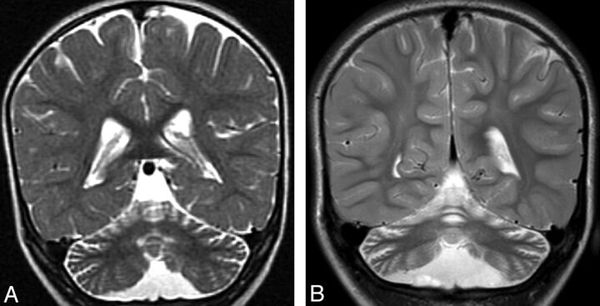

При синдроме Ретта структура белка нарушается, что приводит к его плохой работе. Страдает рост и развитие головного мозга, а кора больших полушарий и мозжечок атрофируются (уменьшаются) [11]. Истончение коры головного мозга приводит к сбоям в работе центров речи и контроля за поведением и планированием движений, а атрофия мозжечка вызывает проблемы с координацией и тремор.

![Атрофия мозжечка и коры головного мозга [25] Атрофия мозжечка и коры головного мозга [25]](/media/bolezny/sindrom-retta/atrofiya-mozzhechka-i-kory-golovnogo-mozga-25_s_KI5QZBE.jpeg)

Атрофия мозжечка и коры головного мозга [25]